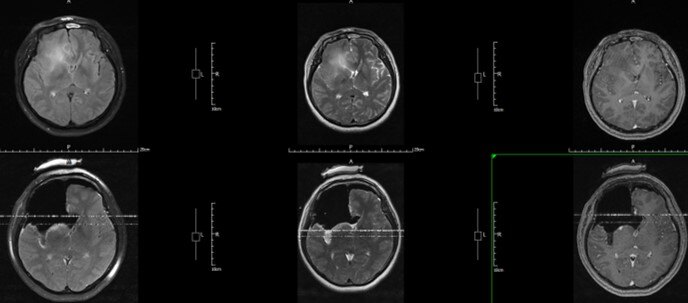

考虑到患者的肿瘤2年时间再次进展,此次可能已经恶性进展为高级别胶质瘤,此次我们以Flair作为边界切除肿瘤,全切除影像学异常部分。按照最新的(2021年)标准,术后病理:星形细胞瘤,IDH 突变型,WHOIV级。建议替莫唑胺同步放化疗。

术中T2 Flair

术中T2

术前 VS 术中